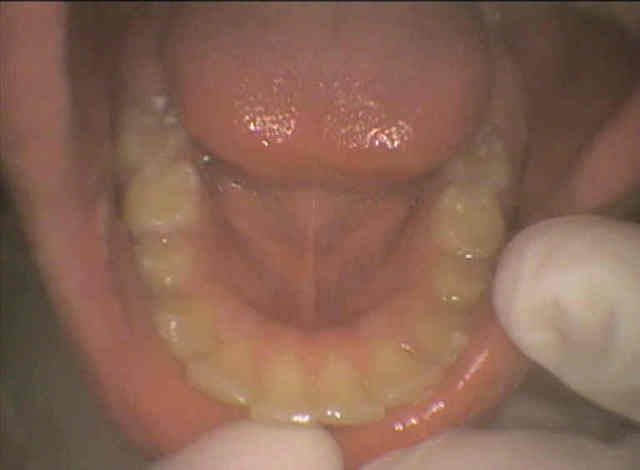

Pourriez vous me donner un avis : patient de 13 ans , le traitement odf proposé est extractions des 4 PM et des 8.

Sans relancer un nouveau debat entre écoles opposées , y a t'il unanimité quand à la pertinence du traitement proposé ?